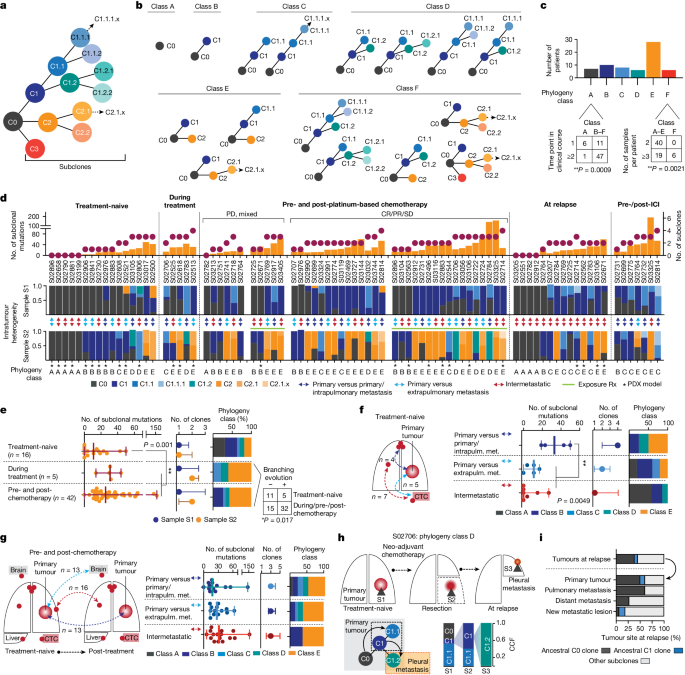

Aiming to shed light on the dynamics of genome evolution in metastatic SCLC, we performed genome sequencing of all tumour specimens to identify genomic alterations. Whole-exome sequencing data at an average coverage of 127-fold were used to compute cancer cell fraction (CCF) for somatic mutations, a metric of relative abundance of mutant alleles corrected for purity, ploidy and absolute copy number, which affords the assignment of mutations to individual tumour clones and enables tracking of single clones in spatially and temporally distinct tumours 15 ( Methods ). We assigned mutations to the most recent common ancestor (C0) if mutations were shared and clonal with CCFs of 100% across all samples analysed, and to subclones (C1, C2 and C3) if clusters of mutations were either private to specific tumour sites or found at lower CCF. We thus reconstructed the clonal lineage and determined tumour phylogenies for all 65 patients ( Supplementary Appendix , Supplementary Tables 2 and 4 and Methods ).

Previous genomic studies conducted for single tumour sites obtained from treatment-naive patients indicated low levels of genomic intratumour heterogeneity in SCLC compared with lung adenocarcinoma 5 . Through analysis of spatially and temporally distinct tumours, we now observed a wide range in the absolute number of subclonal mutations and subclones previously observed in other cancers as well 16 (Extended Data Fig. 1a,b ). Tumour phylogenies across all patients exhibited patterns of linear and branched evolution, in some cases indicating a sequential acquisition of genome alterations and thereby giving rise to a dominant clone. In other patients, emerging subclones branched from ancestral clones thus creating multiple lineages 16 . For systematic study of the evolutionary patterns we assigned tumour phylogenies to distinct classes (Fig. 2b,c ): class A, if no subclones were identified, which was frequently observed when comparing more than one anatomic site at a single time point (Fisher’s exact test, ** P < 0.01; Fig. 2c ); classes B and C, with one or at least two subclones, respectively, compatible with linear phylogenies; classes D and E, phylogenies with one branching event in which tumour clones descend from either C1 subclones (class D) or the common ancestral clone C0 (class E); and class F, phylogenies with at least two branching events exclusively identified in patients, with higher numbers of specimens referring to at least three spatially or temporally distinct tumours (Fisher’s exact test, P < 0.001; Fig. 2c and Extended Data Fig. 1c ), thus providing further information on phylogenetic complexity. To permit interpatient comparisons we therefore sought to perform paired analyses, considering a maximum of two samples per patient (Fig. 2d and Extended Data Table 1 ), which did not show any significant change in the absolute number of subclonal mutations but led to reduced phylogenetic complexities assigned to classes A–E ( Methods and Extended Data Fig. 1a,b ). We thus observed a significantly lower clonal diversity in treatment-naive patients across different tumour sites than in temporally and spatially distinct tumours from patients undergoing treatment (** P < 0.01; Fig. 2d,e ). Consequently the genomic heterogeneity of the tumour—although limited at diagnosis—increased markedly as a result of therapeutic intervention.

a , Schematic of clone phylogeny depicting the most recent common ancestral clone, C0, descending C1, C2 and C3 and subsequent subclones numbered accordingly. b , Phylogeny classes: class A, no subclones; linear phylogenies with one subclone (class B) or at least two subclones (class C); phylogenies with one branching event from C1 subclones (class D) or the common ancestral clone C0 (class E), or at least two branching events (class F). c , Number of samples and distinct time points associated with phylogeny class for each patient (Fisher’s exact test, two-sided, ** P < 0.01). d , Tumour phylogenies at distinct clinical scenorios determined for each patient from paired analyses of WES data (samples S1 and S2; Fig. 1c and Methods ), sorted according to the number of clones and subclonal mutations (top), showing site-specific CCF of identified clones (intratumour heterogeneity, middle) and phylogeny class (bottom). Cases pre- and post-platinum-based chemotherapy are sorted according to clinical response and exposure of tumour sites to radiation (Rx, green line). Double-headed arrows represent comparisons of distinct samples from the primary tumour and either intrapulmonary metastases (dark blue) or extrapulmonary metastases (light blue), or within intermetastatic sites (red). Asterisks mark samples from PDX models. e – g , Subclonal mutations, tumour clones and phylogeny class (median with whiskers representing minimum and maximum values) under distinct clinical scenarios. e , Branching evolution (classes D and E). Fisher’s exact test, two-sided, * P < 0.05. f , g , Spatially distinct sites from treatment-naive setting ( f ) and pre-/post-first-line platinum-based chemotherapy ( g ). ** P < 0.01; Mann–Whitney U -test, two-sided, not significant. h , Clonal dynamics of patient S02706 for tumours acquired before (S1), after neo-adjuvant chemotherapy (S2) and at relapse (S3). i , Proportion of ancestral C0 or C1 clones in relapsing tumours.

We sought to determine the subclonal composition at the time of first diagnosis to study the evolutionary dynamics of tumour progression in a highly metastatic disease. Our analysis in these treatment-naive patients included spatially distinct intra- and extrapulmonary sites exhibiting either no evidence of subclones (class A) or limited mutational changes with patterns of linear evolution (Fig. 2d , left). Clonal diversity was lower when comparing metastatic sites with one another, which frequently included CTC-derived tumours and confirmed earlier observations 12 , 13 . However, tumour regions simultaneously obtained from the primary site and intrapulmonary metastases exhibited increased subclonal mutations (** P < 0.01) and branched evolutionary processes (classes D and E; Fig. 2e ). Thus, following the successful establishment of metastases, the subclonal composition appeared largely unchanged. Additionally, increased clonal heterogeneity and ongoing evolution appeared to occur during the first steps of metastatic seeding in the physical proximity of the original founder clone, driving the outgrowth of one rapidly expanding tumour.

We next analysed the impact of chemotherapy on the dynamics of tumour evolution and compared tumours before therapy with tumour sites acquired during treatment and at the time of relapse. Most tumours exhibited clonal branching from ancestral clones C1 or C0 (67%, n = 31 of 46, P < 0.05) under therapy, causing increased site-specific intratumour heterogeneity (sample 2; Fig. 2d,e ) and spatial clonal diversity when comparing specimens sampled simultaneously from different sites at relapse (** P < 0.01; Extended Data Fig. 1d ). In two patients we tracked the evolutionary processes at the site of the primary tumour before and during therapy, following neo-adjuvant chemotherapy and at the time of subsequent relapse (Fig. 2h and Extended Data Fig. 1e ). In both cases we found phylogenies of class D showing several distinct clones at the site of the primary tumour and repression of the initial dominating clone by chemotherapy, followed by the emergence and expansion of subclones descending from ancestral clone C1 that had caused relapse. Class D phylogenies were frequently identified in comparison with primary lung specimens (Fig. 2g ; n = 6 of seven cases), again emphasizing that the site of the primary tumour serves as a source for ancestral clones that cause metastatic seeding and tumour recurrence. At relapse, both tumour sites exposed to treatment and newly formed metastatic lesions harboured a substantial fraction of pre-existing ancestral clones, most frequently the common ancestor C0 ( n = 16 of 42, 38%), confirming its critical role in relapse (Fig. 2i ). Because these branching events were frequently detected in comparisons from different sites, we next analysed repeated biopsies from the same site over time ( n = 9) and found branching events and the presence of ancestral clones at relapse in these as well (Extended Data Fig. 1f ). Furthermore, focusing the analysis on samples derived from xenotransplant models similarly showed a significant increase in subclonal mutations following treatment (Extended Data Fig. 1g ), suggesting no bias with regard to sample type.

Our data thus suggest that neither is the observed level of evolutionary heterogeneity driven by different anatomic sites nor does first-line chemotherapy primarily drive linear evolution of tumour clones to the state of relapse. By contrast, our data support the view that one highly proliferating clone dominates the tumour at the time of first diagnosis, representing pseudo-clonality 16 which is then suppressed and eliminated by therapy. At clinically overt recurrence, a multitude of subclones has emerged that are driven by the most recent common ancestor, which markedly increases spatial and intratumour heterogeneity.